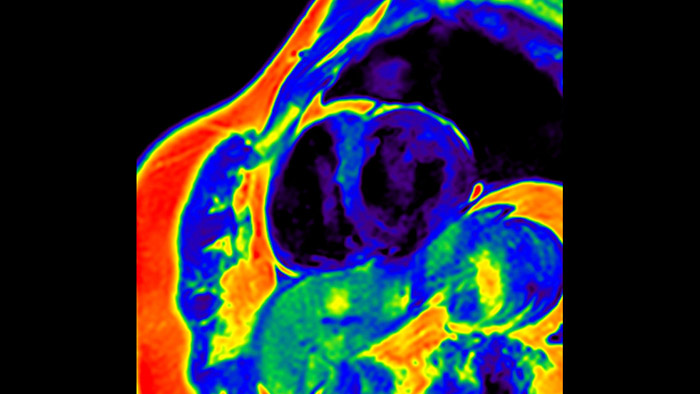

IntelliSpace Portal MR Caas5,6 Strain7 assists in patient diagnosis and monitoring by providing global strain parameters such as global longitudinal strain (GLS), global circumferential strain (GCS), and global radial strain (GRS), using short and long axis MR images, as well as describing the myocardium deformation- such as shortening, thickening, and lengthening during the cardiac cycle.